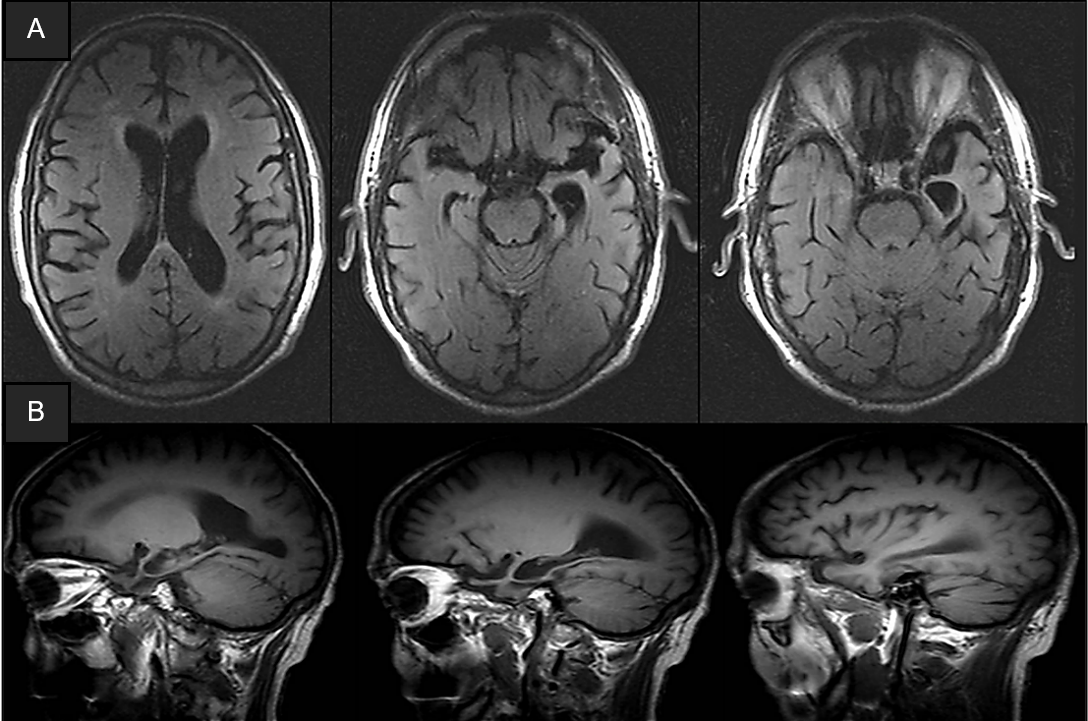

Results: A 78-year-old man presented with a six-year history of progressive memory decline, initially marked by difficulty with recent memory and mild anomia, evolving into motor clumsiness, gait impairment, language difficulties, and behavioural changes. Asymmetric parkinsonism emerged in later stages. Brain imaging revealed left temporal lobe atrophy and frontotemporal hypometabolism, with a negative amyloid PET, leading to a diagnosis of frontotemporal dementia [Figure 1 and 2]. Genetic analysis by exome sequencing revealed a mutation in the SQSTM1 gene (c.1210A>G; p. (Met404Val). Post-mortem brain autopsy confirmed frontotemporal lobar degeneration with atypical TDP-43 protein distribution, along coexisting with tau and Lewy body pathology [Figure 3].

Figure 1. Brain MRI